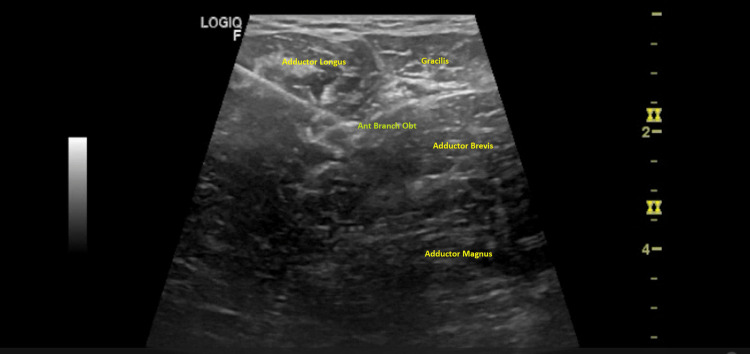

Before the procedure, the patient was positioned supine, and the anterior and posterior branches of the obturator and motor branches to the rectus femoris of the femoral nerves were identified using a 3.7-13 MHz linear probe (Logiq™ P8 ultrasound machine, GE Healthcare, Chicago, Illinois, United States). The anterior branch of the obturator nerve was identified in the fascial plane between the adductor longus and adductor brevis, the posterior branch of the obturator nerves between the adductor brevis and adductor magnus and the femoral nerve at the femoral neurovascular bundle, over iliacus muscle and proximal to the origin of the direct head of the rectus femoris.

Figure 1. Anterior branch of obturator nerve.

Anterior branch of the obturator nerve in the fascial plane between the adductor longus and adductor brevis. Tip of the needle near the anterior branch of the obturator nerve (Ant Branch Obt).